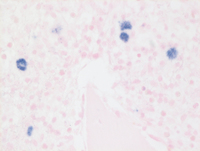

EBV ISH in CHL

On this EBV in situ hybridization stain,only the scattered Hodgkin cells are positive for EBV. This pattern of EBV restricted only to the large neoplastic cells is typical of the pattern expected in classical Hodgkin lymphoma as opposed to EBV-positive diffuse large B-cell lymphoma, not otherwise specified wherein there is a spectrum of EBV+ cells ranging from small to large. This pattern allows the distinction of EBV positive classical Hodgkin lymphoma and EBV+DLBCL, NOS.